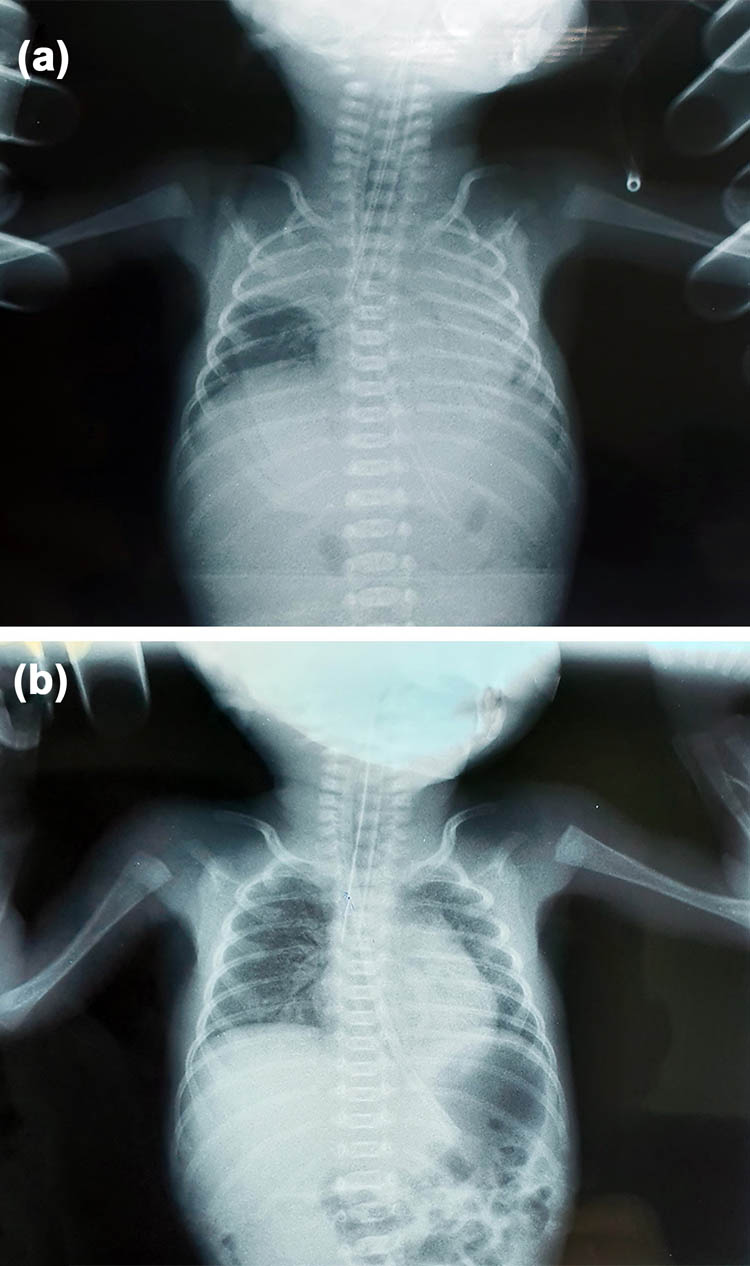

The patient was admitted to the hospital at 24 + 5 WG for scant vaginal bleeding, lower abdominal pain, and body temperature up to 37.5°C. Gynecological examination revealed bleeding within dilatation of the cervix with a diameter of 1 cm near the cerclage. The laboratory analyses revealed leukocytosis with elevated C-reactive protein (CRP) (28.3 × 109/L white blood cells (WBCs), 3.50 × 109/L red blood cells (RBCs), 108 g/L hemoglobin (Hgb), 385 × 109/L platelet count (PLT), and 28.5 mg/L CRP. Other laboratory analyses were in range with reference values. Treatment was initiated with intravenous administration of ceftriaxone at a dose of 2 g/day. Immediately after admission, fetal membranes spontaneously ruptured, and the mother experienced uterine contractions. The cerclage was removed, and an extremely preterm dichorionic female twin birth with discordant FGR occurred at 25 + 0 WG. The first twin weighed 560 g and had an AS of 2/2, and the second twin weighed 780 g and had an AS of 2/2. Both female infants had an altered state of consciousness and were edematous, hypotonic, apneic, and bradycardic, with multiple hematomas at the extremities and in the occipital region, and had leukocytosis (95.6 × 109/L WBCs in the first and 38.9 × 109/L WBCs in the second newborn). Swabs of the umbilical cord, nose, and anus were negative for both infants. Chest X-ray of the first newborn showed decreased transparency of the pulmonary parenchyma to the left with a clearly limited presence in the upper lobe area to the right (Figure 1a). Radiography of the second infant confirmed individual paracardial and basal shadings of the pulmonary parenchyma (Figure 1b). Ultrasound indicated the immaturity of the brain parenchyma in both newborns with asymmetry of the ventricular system and plexus. Both infants were attached to mechanical ventilation, followed by treatment with electrolytes, a prophylactic dose of corticosteroids, and antibiotic therapy. The infants died two days after birth due to respiratory failure despite resuscitation.

Chest X-ray of the newborns. (a) Image shows decreased transparency of the pulmonary parenchyma to the left with a clearly limited presence in the upper lobe area to the right in the first newborn; (b) chest X-ray shows individual paracardial and basal shadings of the pulmonary parenchyma in the second newborn.